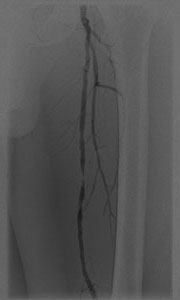

静脈のカテーテル治療

深部静脈血栓症(DVT)という病気があります。これは静脈という全身から心臓に戻ってくる血管に血栓ができ閉塞することにより、下肢の浮腫、発赤、疼痛といった症状が出現し、人によってはその血栓が肺動脈に飛び肺塞栓症という命にかかわる病気につながることもあります。通常は抗凝固薬という血栓を徐々に溶かす内服薬を服用しますが、完全に閉塞した血管の中には薬剤が到達しにくく、症状の改善には数か月を要す場合が多く、これにより血栓後後遺症という、下肢の浮腫、だるさ、ひどい場合には皮膚の潰瘍などの後遺症を残すことがあります。当院ではカテーテル血栓溶解療法(CDT)と呼ばれる、血栓の中に細いカテーテルを留置し血栓溶解剤を直接血栓に向け噴射する治療を以前から積極的に行っております。これにより多くの場合は血栓の早期の溶解が得られ、自覚症状が大幅に早く改善し、血栓後後遺症を減らすことができます。深部静脈血栓症(DVT)の方全員が適応となるわけではなく、症状が強い場合に限定される治療です。

血栓内に留置し、多方向に血栓溶解剤を直接噴射し血栓を溶かすことができる血栓溶解用カテーテル

(画像提供:メリットメディカル社)